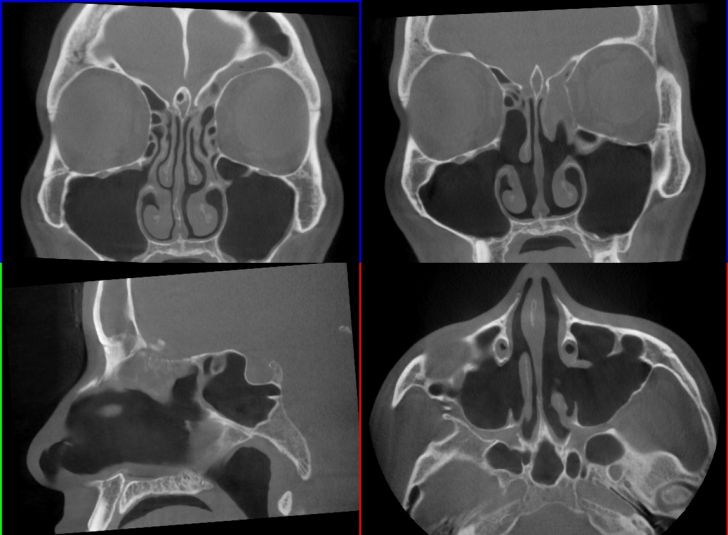

実際の自分のCT画像です。

まずは一度目の手術を行う前の、何も処置をしていない僕の副鼻腔のCT画像です。

▼2015年5月のCT画像

慢性の副鼻腔炎であることが分かっている程度で、とにかく頭痛がひどかった時期です。

画像右上の部分(前頭洞)が灰色になっていて、そこに膿が溜まっていました。

あくまで病院の先生に聞いた話をまとめているだけですが、左目の上に膿が溜まっていて炎症を起こしており、それが頭痛の原因でした。

良く膿が溜まると言われている上顎洞(じょうがくどう)と呼ばれるところには、全くと言っていいほど膿はありませんでした。

2015年8月の副鼻腔

その後8月頃に一度頭痛が悪化したことがあったため、その時にもCTを撮影しました。

その時の画像です。

▼2015年8月のCT画像

1度目の手術で鼻の中央辺りがかなり変わったことが分かります。

手術前の画像と比べてもらえれば分かりますが、複雑に迷路のようになっていた鼻の中央がごっそり削られてなくなっています。

こうやって鼻の通り道をよくして、膿が排出されやすくするための手術だったわけですね。

ただ、前頭洞周辺にある膿が排出されているのかはこの画像では判別しにくかったです。

2016年11月の副鼻腔

その時にもCTを撮影しましたが、その画像はもらえなかったので2015年8月のCTを違う角度から見た時の画像です。

▼それがこちら

【画像解説】

上記画像の通り、左前頭洞にはまた膿が溜まっていました。

これによって左前頭洞周辺が炎症を起こし、神経を圧迫して頭痛が起こっているとのこと。

また右側の前頭洞は全くもって膿は溜まっておらず、正常な状態でしたが、悪くはないけど異常発達があるとのこと。

そして緑色のところが、前頭洞と鼻の穴をつないでいる通り道でしたが、ここにも一般の人と比べると違いがあると言われました。

➀前頭洞の空洞の発達が一般的な人の2倍!

前頭洞とはおでこ周辺のあたりのことを差し、大体は目じり辺りまでが空洞になっている程度が一般的だそうです。

僕の場合、前頭洞としての空洞がこめかみの後ろ辺りの方まで発達しているとのことでした。(悪いことはなくてむしろ良いらしい…ホントかは分かりませんが)

➁右前頭洞が左にはみ出ている

前頭洞は左右にありますが、左右対称ということはほとんどないみたいです。

上記画像を見てもらっても分かりますが、青枠で囲ったところが真ん中より少し右の方に出ています。(画像左側が顔の右部分になります)

このおかげで左前頭洞が押しやられて、少し狭くなる現象が起こります。

③左前頭洞の膿を排出するはずの通り道が一般的な人の2分の1!

右前頭洞が左にのびているおかげで、左前頭洞の空洞が狭くなっているとの事でした。

そもそもこの通り道は他の副鼻腔と比べると狭い通り道なんだそうですが、このせいで僕の左前頭洞の膿を排出するべき通り道の広さは、一般的な人の2分の1しかないんだとか。

これが頻繁に左前頭洞に膿が溜まって炎症を起こす原因だったんです。